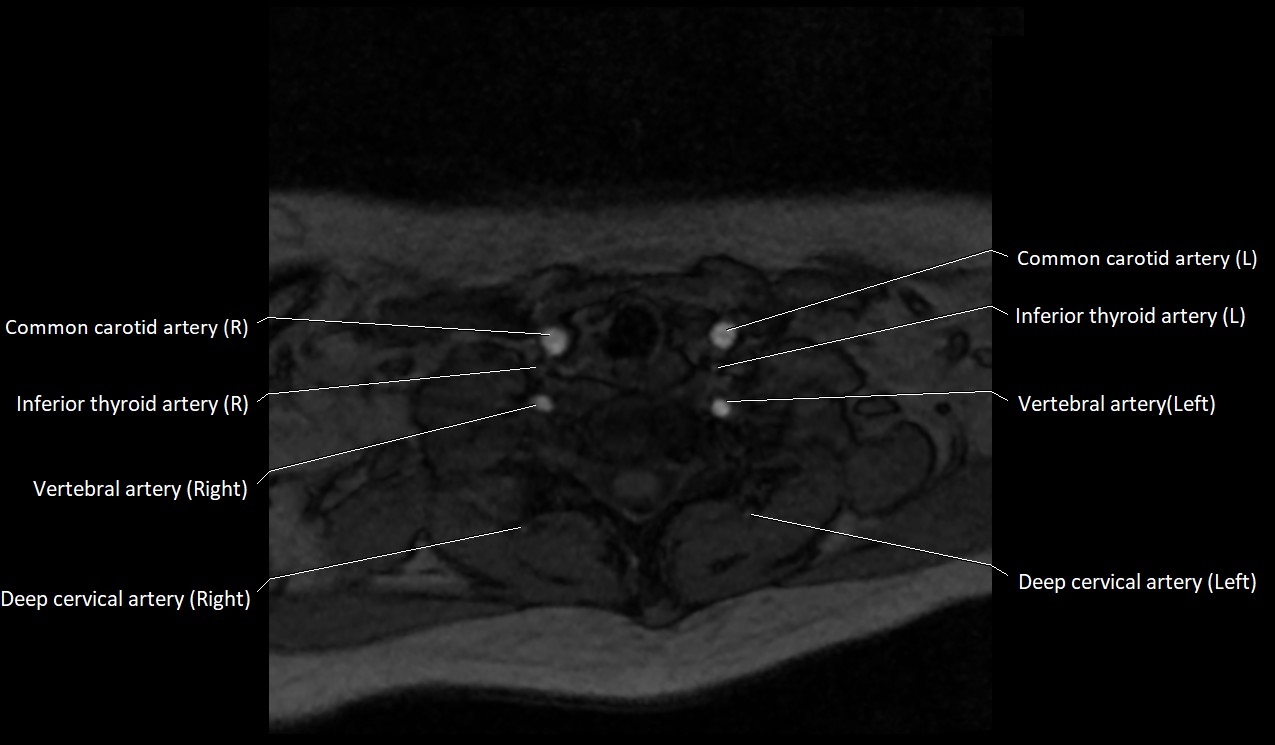

MRI images

image